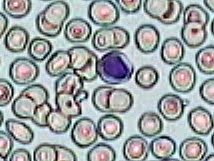

Práctica de Frotis sanguíneo 7